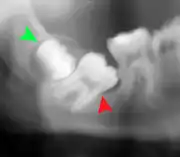

If the tooth cannot be assessed with clinical exam alone, the diagnosis is made using either a panoramic radiograph or cone-beam CT. Where unerupted wisdom teeth still have eruption potential several predictors are used to determine the chance of the teeth becoming impacted. The ratio of space between the tooth crown length and the amount of space available, the angle of the teeth compared to the other teeth are the two most commonly used predictors, with the space ratio being the most accurate. Despite the capacity for movement into early adulthood, the likelihood that the tooth will become impacted can be predicted when the ratio of space available to the length of the crown of the tooth is under 1.[5]: 141

Impacted wisdom teeth are classified by their direction of impaction, their depth compared to the biting surface of adjacent teeth and the amount of the tooth's crown that extends through gum tissue or bone. Impacted wisdom teeth can also be classified by the presence or absence of symptoms and disease. Screening for the presence of wisdom teeth often begins in late adolescence when a partially developed tooth may become impacted. Screening commonly includes a clinical examination as well as x-rays such as panoramic radiographs.

| Diagnostic method | Examination, x-ray |